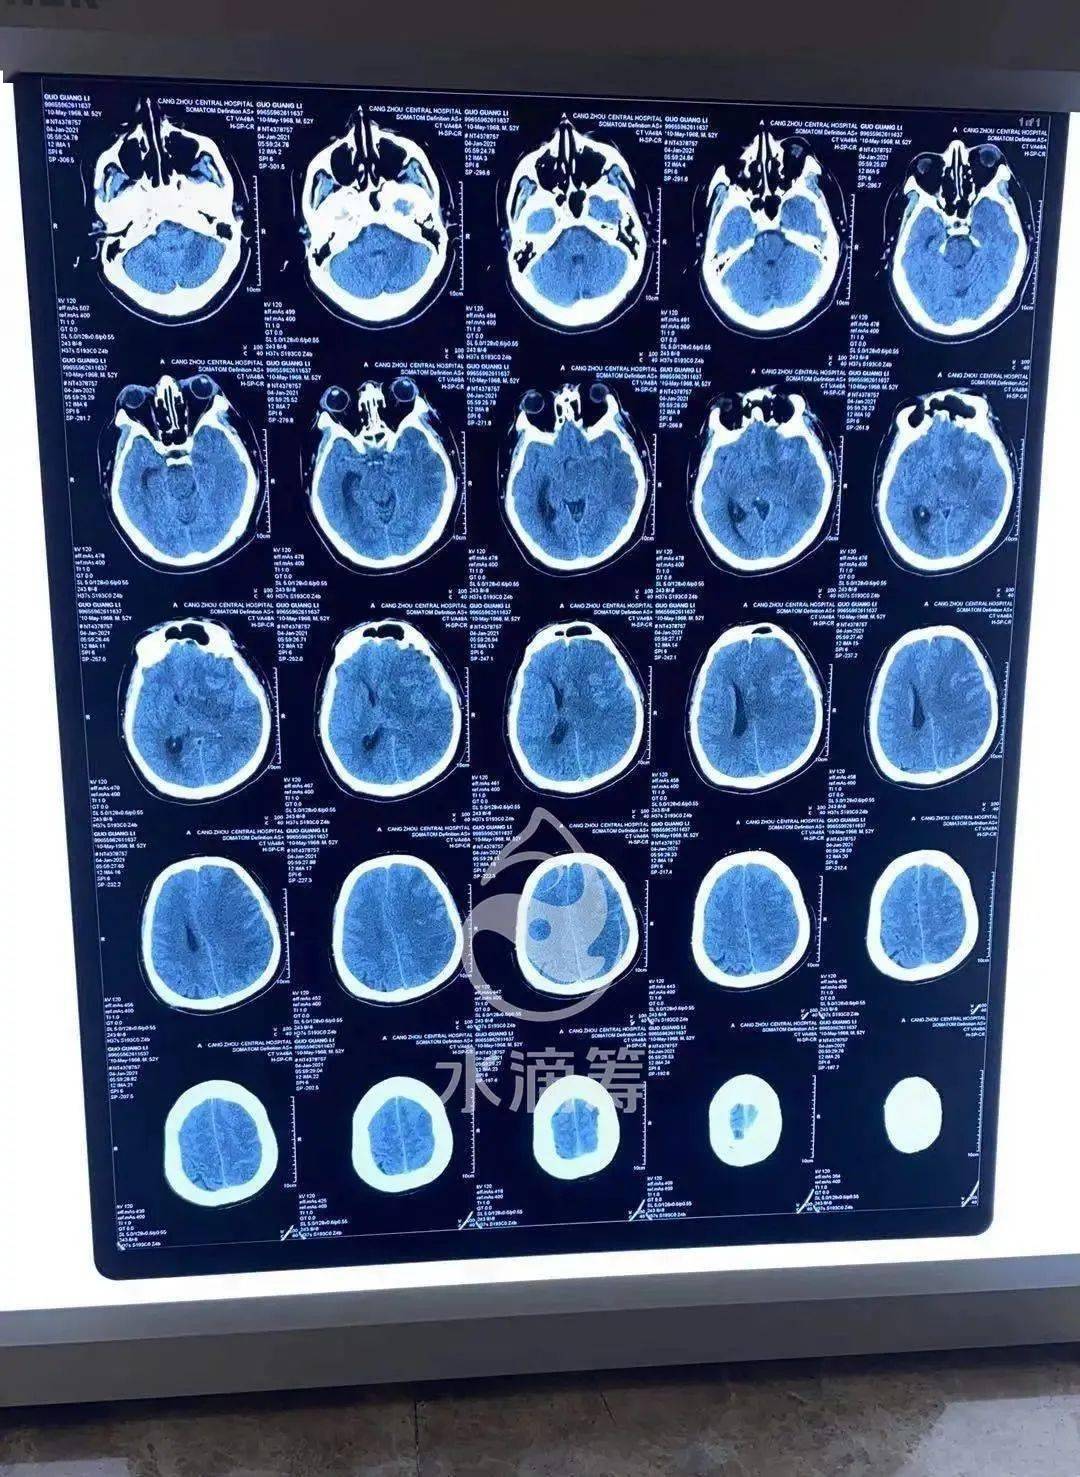

颅脑ct怎么读神经科医生必备